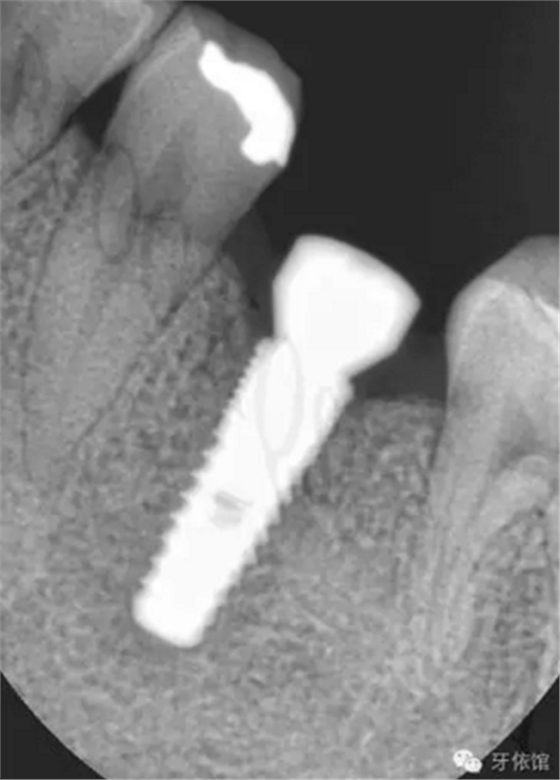

術(shù)后三個(gè)月的X光片。